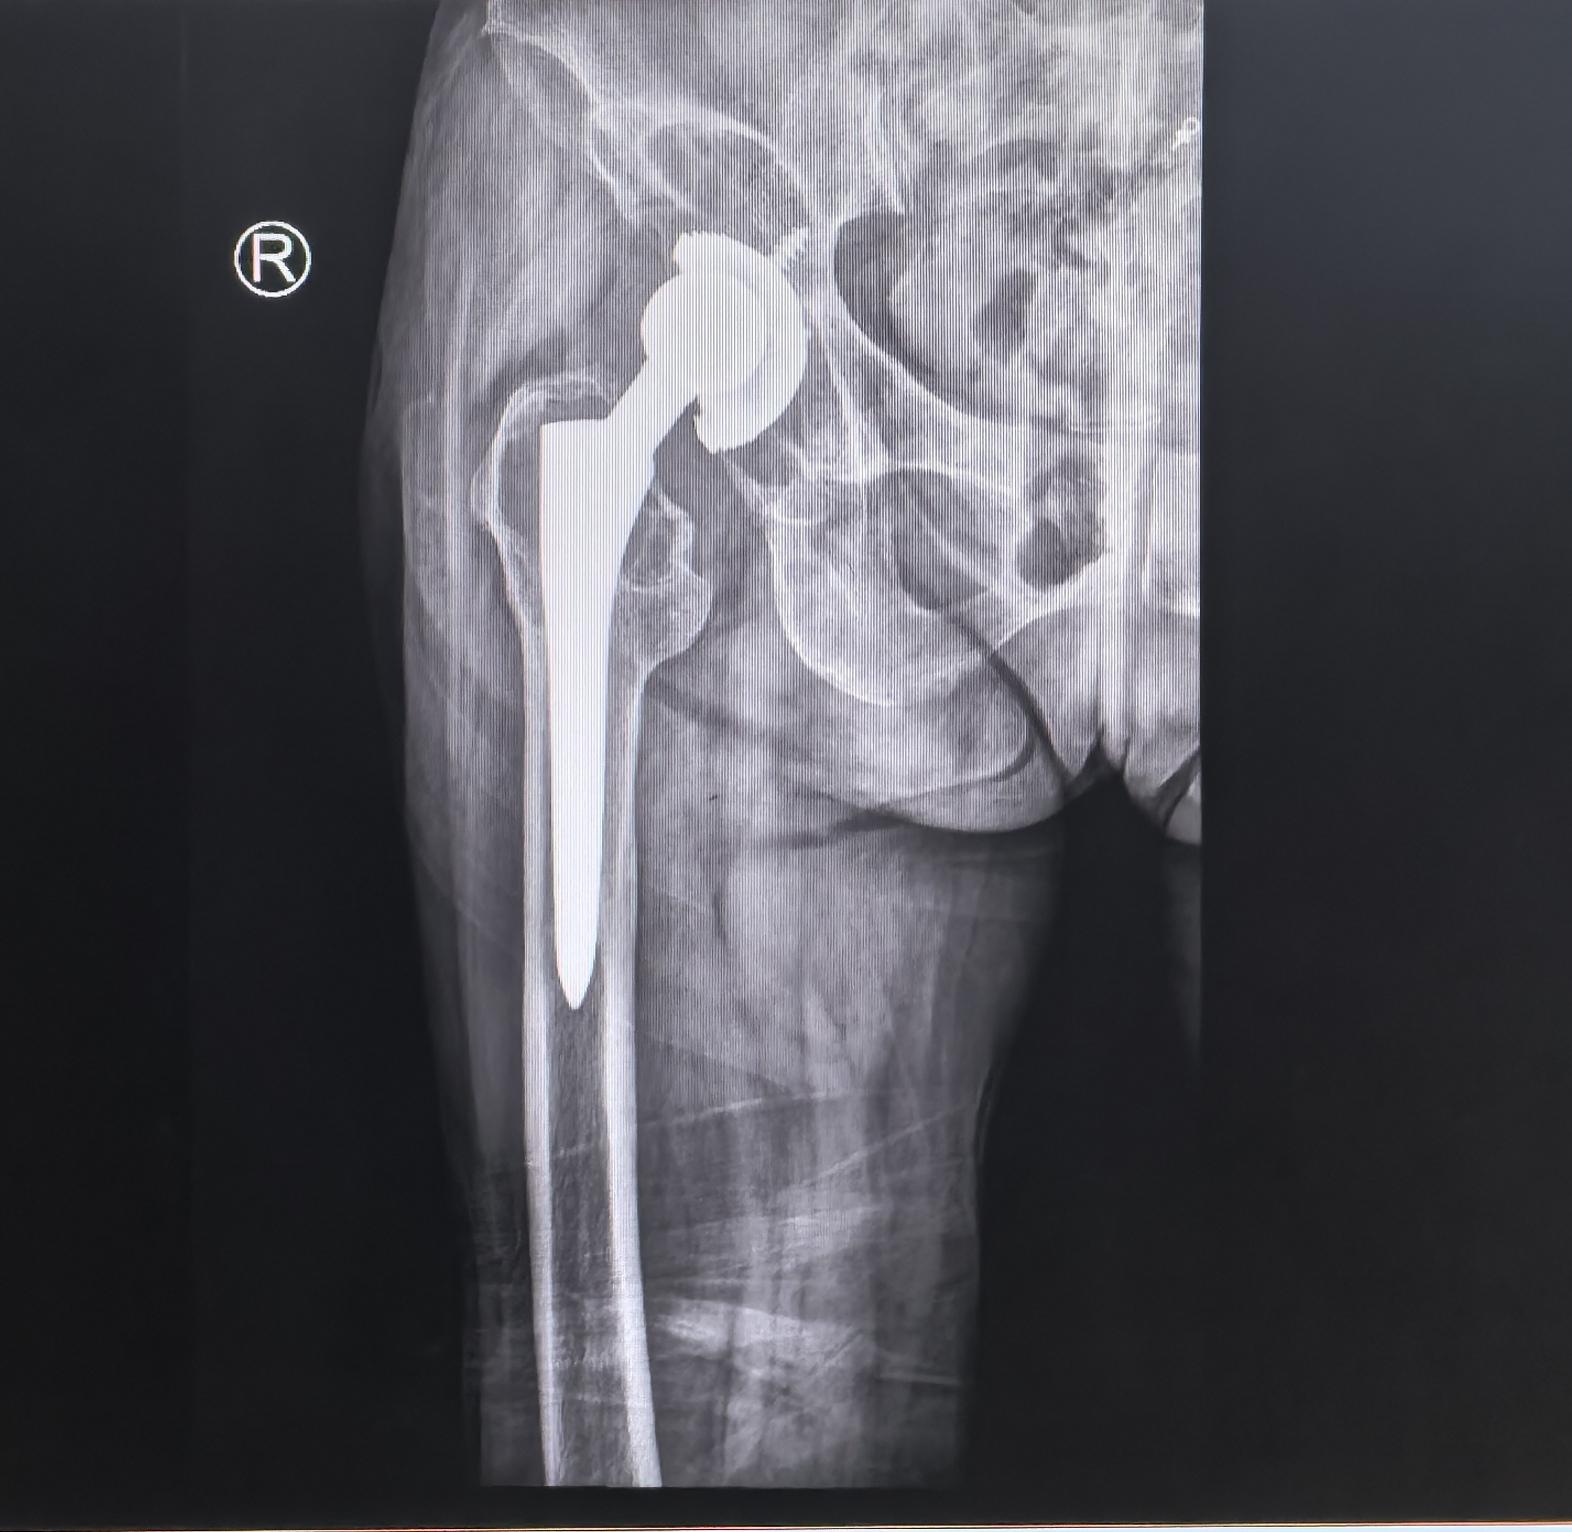

全髋关节翻修术。82岁老太太,THA后(14年)假体松动、骨溶解,全髋翻修,再续20年🌹